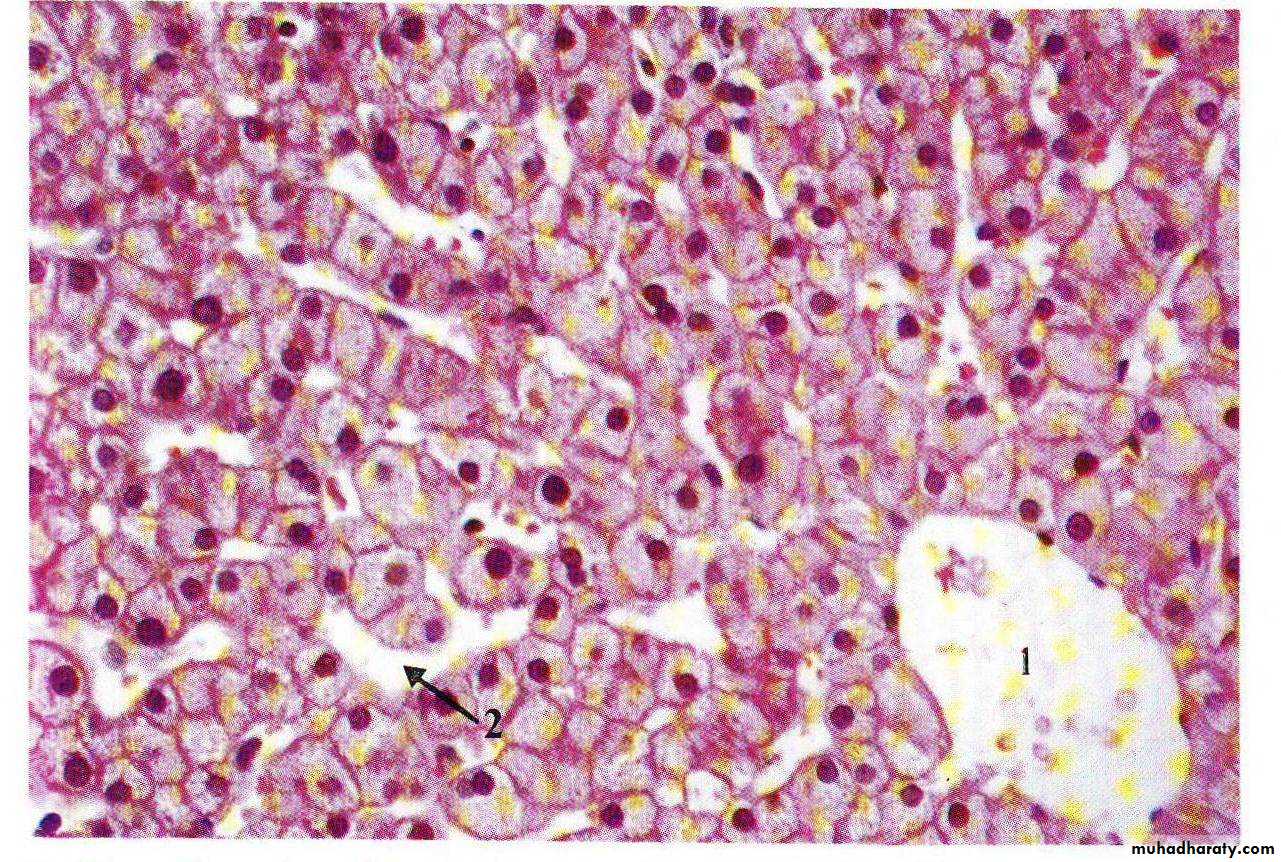

• Pathology

• Fatty liver• Alcoholic hepatitis – Mallory’s hyaline